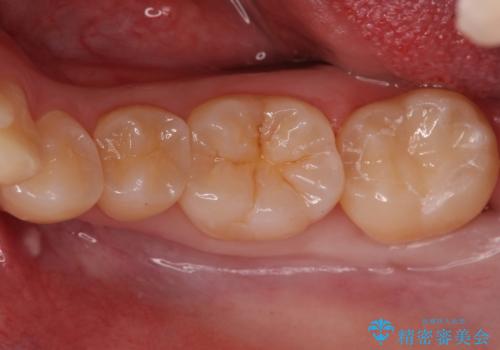

奥歯の虫歯 セラミックインレーでの治療

- 左下7 セラミックインレー 77,000円費用は治療当時の料金となります

削る前は小さな虫歯に見えますが、歯の中で進行しつつある虫歯でした。

虫歯が大きくなると必要な治療が増えてえしまうため早期発見、早期治療を行うことが大事になってきます。